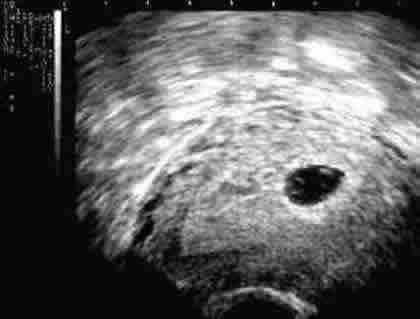

What Can I See on Ultrasound at 5 Weeks?

On your 5 weeks pregnant ultrasound, you should be able to see your gestational sac and the yolk sac which is always present when you are 5 weeks pregnant. If you are carrying fraternal twins, you will be able to see the yolk sac as well as the fetal poles in two separate sacs. However, if you are carrying identical twins, you will be able to see a single gestational sac and two yolk sacs and the embryo is about 1.25mm long.

The gestational sac is that black area, while the yolk sac is the small white circle you see at the sac’s upper left. The yolk sac is the source of nutrients for the fetus. In size, the gestational sac at five months is about 6 to 12 mm and while the embryo is present, you cannot see it as it is the size of a rice grain.